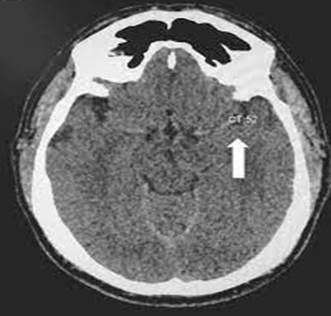

Figura 1: Tomografia axial computada simple de cráneo cortes axiales, aprecia el signo de la cuerda en el circuito medio izquierdo

El examen neurológico preliminar no mostró signos cerebelosos positivos, el examen físico y el estudio diagnóstico final confirmó un isquémico del territorio de la cerebral media izquierda secundario a  hiperhomocisteinemia ya que el protocolo diagnostico no mostro causas arrítmicas, aterotromboticas ni malformaciones vasculares, no foramen ni comunicaciones interventriculares o auriculares, en base al protocolo (CASCADE, del inglés Childhood Acute Ischemic Stroke Standardized Classification and Diagnostic Evaluation). Esta clasificación se basa en la localización y naturaleza de cualquier alteración anató- mica detectada, tanto en el árbol vascular extracraneal o intracraneal como intracardíaca, que pudiera explicar el ictus en el paciente individual. Exige la realización de las siguientes pruebas diagnósticas: ecocardiograma, imagen vascular (angiografía por resonancia magnética [angio-RM], angiografía por tomografía computarizada [Angio-TC], o arteriografía convencional) y el patrón de distribución anatómica del infarto cerebral en neuroimagen (RM o TC). Las principales categorías diagnósticas son: arteriopatía de pequeño vaso de la infancia; arteriopatía cerebral focal unilateral de la infancia; arteriopatía cerebral bilateral de la infancia; arteriopatía aórtica o cervical; cardioembolia; otros; y multifactorial. Su principal limitación es que, al basarse en enfermedades estructurales de corazón o vasos sanguíneos, no confiere entidad etiológica a las enfermedades inflamatorias, síndromes genéticos, hemoglobinopatías e infecciones o los estados de hipercoagulabilidad. Por otra parte, la concordancia interobservador es solo moderada a pesar de entrenamiento (18).